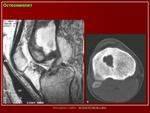

Абсцесс Броди (вялотекущий первично хронический внутрикостный абсцесс; МКБ–10: М86.8 Другой остеомиелит) заболевание, характеризующееся образованием в губчатом веществе эпифиза небольшой полости, заполненной гноем. Чаще у лиц молодого возраста, после окостенения эпифизарной пластинки роста. Локализуется в основном в верхнем или нижнем эпифизе большеберцовой кости, в метафизах бедренной и плечевой костей, реже в других длинных костях, иногда в костях позвоночника, стопы и др..

Клиническая картина. Болезненность при перкуссии кости, появление периодических болей (особенно ночных), протекает вяло с невысокой температурой.

Рентгенологически обнаруживают полость с чёткими склерозированными контурами, при обострении периостальные наслоения, остеосклероз.

Макроскопически. Размеры очага не более 3 – 4 см, полость заполнена гноевидной жидкостью, вокруг очага склерозированная кость, деформация костей минимальная, свищи обычно не образуются.

Микроскопия. Стенка полости образована фиброзной и грануляционной тканью, инфильтрированной плазматическими клетками, эозинофилами, гистиоцитами.

Рентгенологическое исследование имеет решающее диагностическое значение. Все детали патологоанатомической картины абсцесса Броди передаются в точности и на рентгеновских снимках (рис. 207 и 208). Изолированная, правильной округлой формы полость, без секвестра, с резко ограниченными гладкими внутренними контурами, расположенная среди склерозированного губчатого вещества, на типичном месте — в метафизарном конце большой трубчатой кости, слегка утолщенной благодаря периостальным наслоениям, — эта рентгенологическая картина при поддержке клинических симптомов разрешает диагностическую задачу. При этом следует учесть, что между, так сказать, классическим типичным абсцессом Броди и другими формами хронического остеомиелита бывают и переходные формы — и по местоположению, размерам, форме, характеру реактивных изменений в окружности, секвестрации и т. д. Это ведь в природе вещей: классификация показывает всегда несколько условно типичное, жизнь преподносит многообразие, не укладывающееся в строгую жесткую схему. Никоим образом не следует злоупотреблять диагнозом абсцесса Броди и ставить его расширительно, чуть ли не во всех случаях более или менее ясно выраженной полости при обычном хроническом остеомиелите: абсцесс Броди — это совершенно определенное клинико-рентгено-анатомическое понятие, это четкая нозологическая единица, и диагноз оправдан лишь в тех случаях, когда рентгенологическая картина удовлетворяет всем вышеперечисленным критериям.